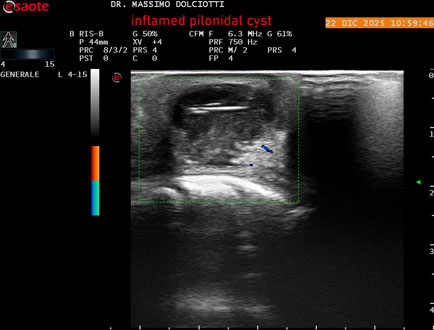

Ecografia del: 22/12/2025

Strumento: Esaote MyLab Eight

Sonda: Lineare Multifrequenza 4-15 MHz

Età Paziente: M 29 anni

Motivazione dell'esame: da 3.giorni dolore, tumefazione ed arrossamento in regione coccigea

Commento all'esame: le immagini ed il video documentano formazione anecogena in sede coccige, delle dimensioni di 24,6 x 18,8 mm, da ricondurre a cisti pilonidale flogosata.

Conclusioni: cisti pilonidale flogosata (inflamed pilonidal cyst).